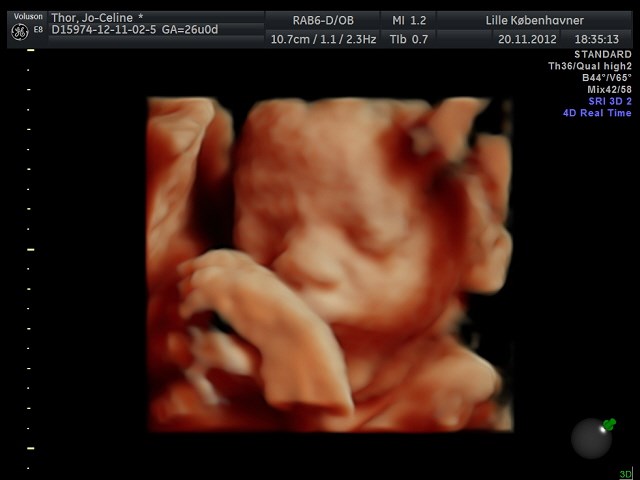

Søger man på Google kommer der kun 3D-billeder.

Så jeg vil høre om nogen herinde har et billede eller to fra uge 28 de vil vise? Og hvor lang var jeres baby, og fik I vægt at vide?